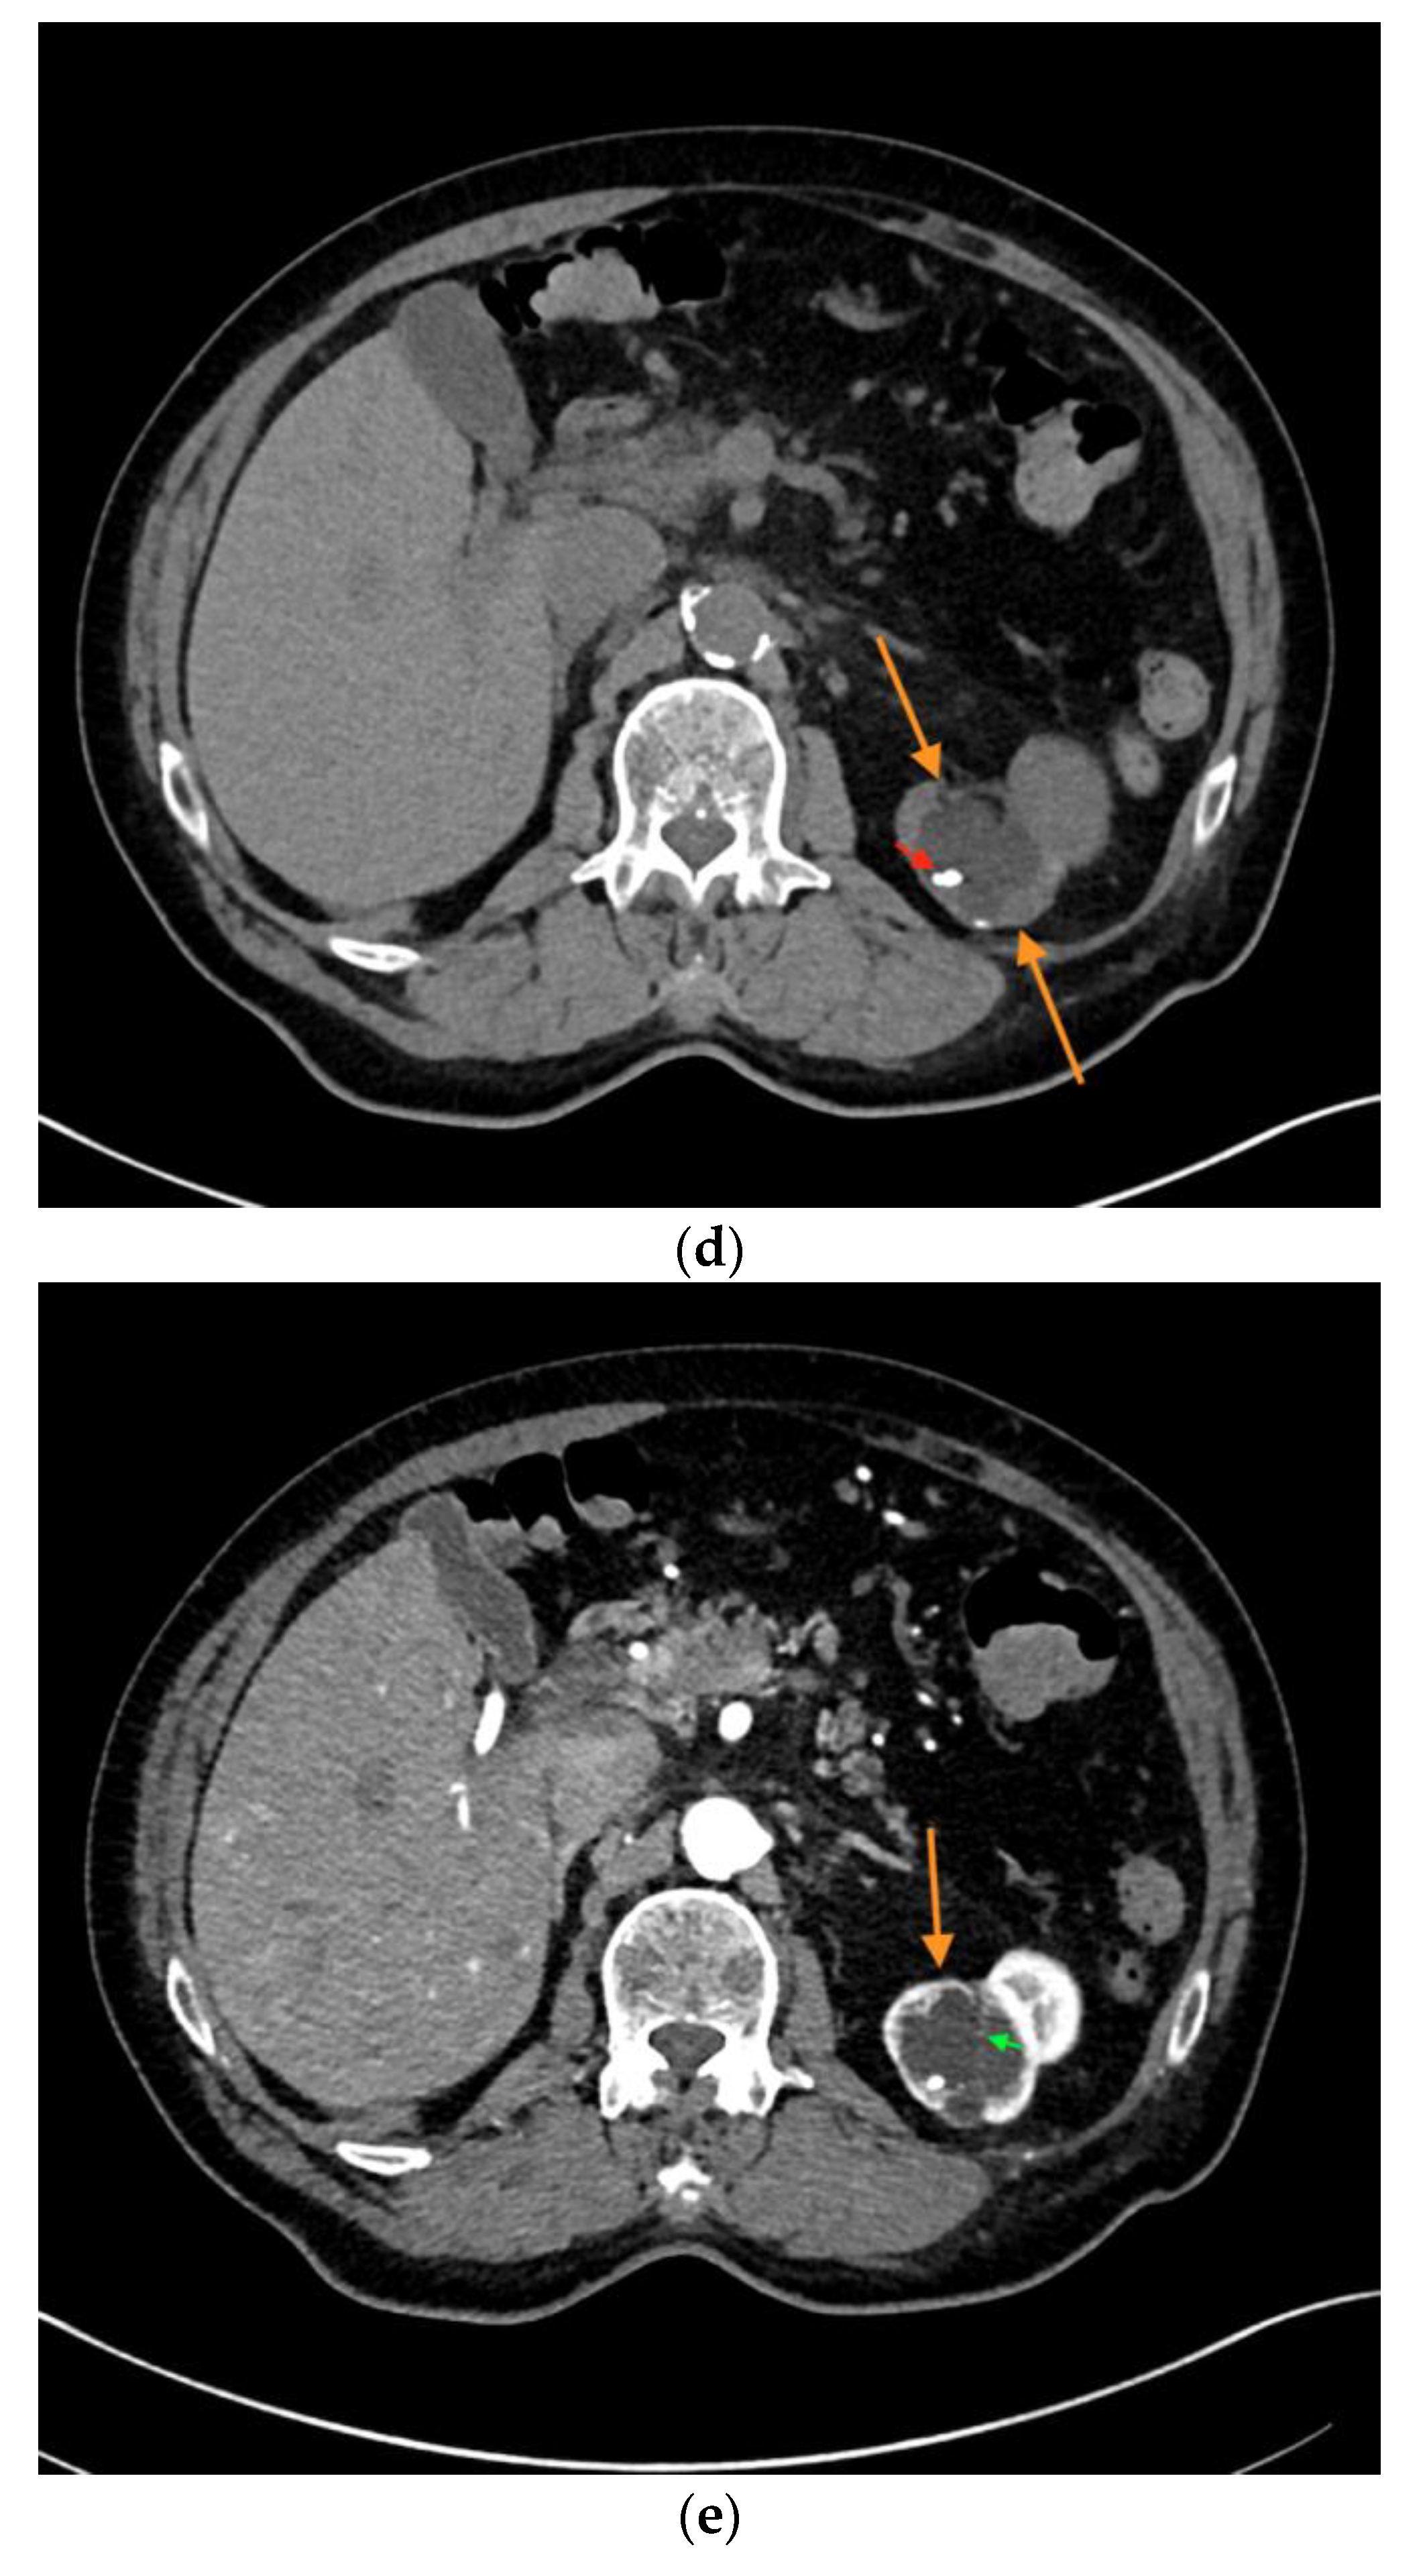

| Patient | Sex | Age | Location | Size (cm) | Native B-Mode | Vascularization (CD) | CEUS | CT | MRI | Treatment: Histopathology |

|---|---|---|---|---|---|---|---|---|---|---|

| #1 | F | 49 | R | 5.6 | Cystic, septated | - | Intraseptal | - | Intraseptal enhancing → Bosniak IIF | Partial nephrectomy: Clear-cell RCC |

| #2 | M | 54 | L | 3.0 | Cystic, hypoechoic areas, wall thickening | - | Peripheral | - | - | Partial nephrectomy: chromophobe RCC |

| #3 | F | 61 | R | 3.5 | Cystic, septated | - | Peripheral, intraseptal | - | - | Partial nephrectomy: clear-cell RCC |

| #4 | F | 43 | R | 1.6 | Cystic | - | Peripheral | - | - | Partial nephrectomy: clear-cell RCC |

| #5 | F | 64 | L | 5.0 | Cystic, focally thickened, septa | - | Intraseptal | - | - | Partial nephrectomy: clear-cell partial cystic RCC |

| #6 | M | 74 | L | 2.0 | Cystic | - | Peripheral, intraseptal | - | - | Partial nephrectomy: clear-cell RCC |

| #7 | F | 66 | L | 7.0 | Cystic, complex | - | Intraseptal | - | - | Partial nephrectomy: multilocular cystic RCC |

| #8 | M | 54 | L | 1.5 | Cystic, wall thickening | - | Intraseptal | - | - | Partial nephrectomy: clear-cell RCC |

| #9 | M | 76 | L | 1.6 | Cystic | - | Peripheral, wash-out | - | - | Partial nephrectomy: papillary RCC |

| #10 | F | 66 | R | 1.5 | Cystic | - | Intraseptal | - | - | Partial nephrectomy: clear-cell RCC |

| #11 | M | 75 | L | 2.7 | Cystic, focally thickened septa | - | Intraseptal | - | - | Partial nephrectomy: Papillary RCC |

| #12 | M | 52 | L | 1.5 | Cystic, focally thickened septa | - | Intraseptal | - | - | Partial nephrectomy: clear-cell RCC |

| #13 | M | 68 | L | 1.5 | Partially cystic | - | Peripheral | - | - | Partial nephrectomy: clear-cell RCC |

| #14 | M | 86 | L | 4.0 | Cystic, septated | - | Intraseptal | Septated, calcified, early enhancement, wash-out in delayed phase → Bosniak III | - | Nephrectomy: cystic clear-cell RCC |

| #15 | M | 63 | R | 2.0 | Cystic | - | Peripheral | - | - | Nephrectomy: clear-cell RCC |

| #16 | F | 62 | L | 2.5 | Partially cystic | - | Peripheral, intraseptal wash-in/wash-out | - | Native MRI: T2w: mainly hyperintense with hypointense septations T1w: hypointense | Renal biopsy: oncocytoma |

| #17 | F | 64 | R | 3.5 | Cystic | - | Intraseptal | - | - | Partial nephrectomy: cystic hamartoma |

| #18 | M | 67 | R | 3.0 | Partially cystic, focally thickened septa | - | Intraseptal | - | - | Partial nephrectomy: cyst, no malignancy |

| #19 | M | 71 | L | 1.2 | Cystic | - | Peripheral | - | - | Partial nephrectomy: cyst, no malignancy |

| #20 | F | 48 | L | 10.0 | Cystic, septated | - | Intraseptal | - | - | Partial nephrectomy: adult cystic nephroma |

| #21 | M | 76 | R | 2.0 | Cystic | - | Peripheral and Intraseptal wash-in/wash-out | - | - | Partial nephrectomy: oncocytoma |

| #22 | M | 46 | R | 0.8 | Cystic | - | Peripheral wash-in/wash-out | - | - | Partial nephrectomy: papillary adenoma |

| #23 | F | 69 | L | 8.0 | Cystic, septated | - | Intraseptal | - | - | Partial nephrectomy: cyst, no malignancy |

| #24 | M | 69 | R | 2.5 | Cystic | - | Peripheral wash-in/wash-out | - | - | Partial nephrectomy: Papillary RCC |

| #26 | M | 66 | R | 5.0 | Cystic | - | Peripheral | - | - | Partial nephrectomy: Hemorrhagic, xantho-granulomatous cyst, no malignancy |

| #27 | M | 67 | R | 7.0 | Cystic, septated, partially calcified | - | Peripheral, intraseptal | Septated, partially calcified → Bosniak IIF | - | Partial nephrectomy: oncocytoma |

| #32 | M | 83 | L | 4.7 | Cystic | - | Peripheral | - | - | Partial nephrectomy: clear-cell RCC |

| #35 | M | 48 | R | 2.5 | Cystic, septated | - | Intraseptal wash-in/wash-out | - | - | Partial nephrectomy: clear-cell RCC |

| #38 | M | 60 | R | 1.2 | Cystic, septated | - | Peripheral | Septated, contrast-enhanced → Bosniak type IIF | - | Partial nephrectomy: clear-cell RCC |